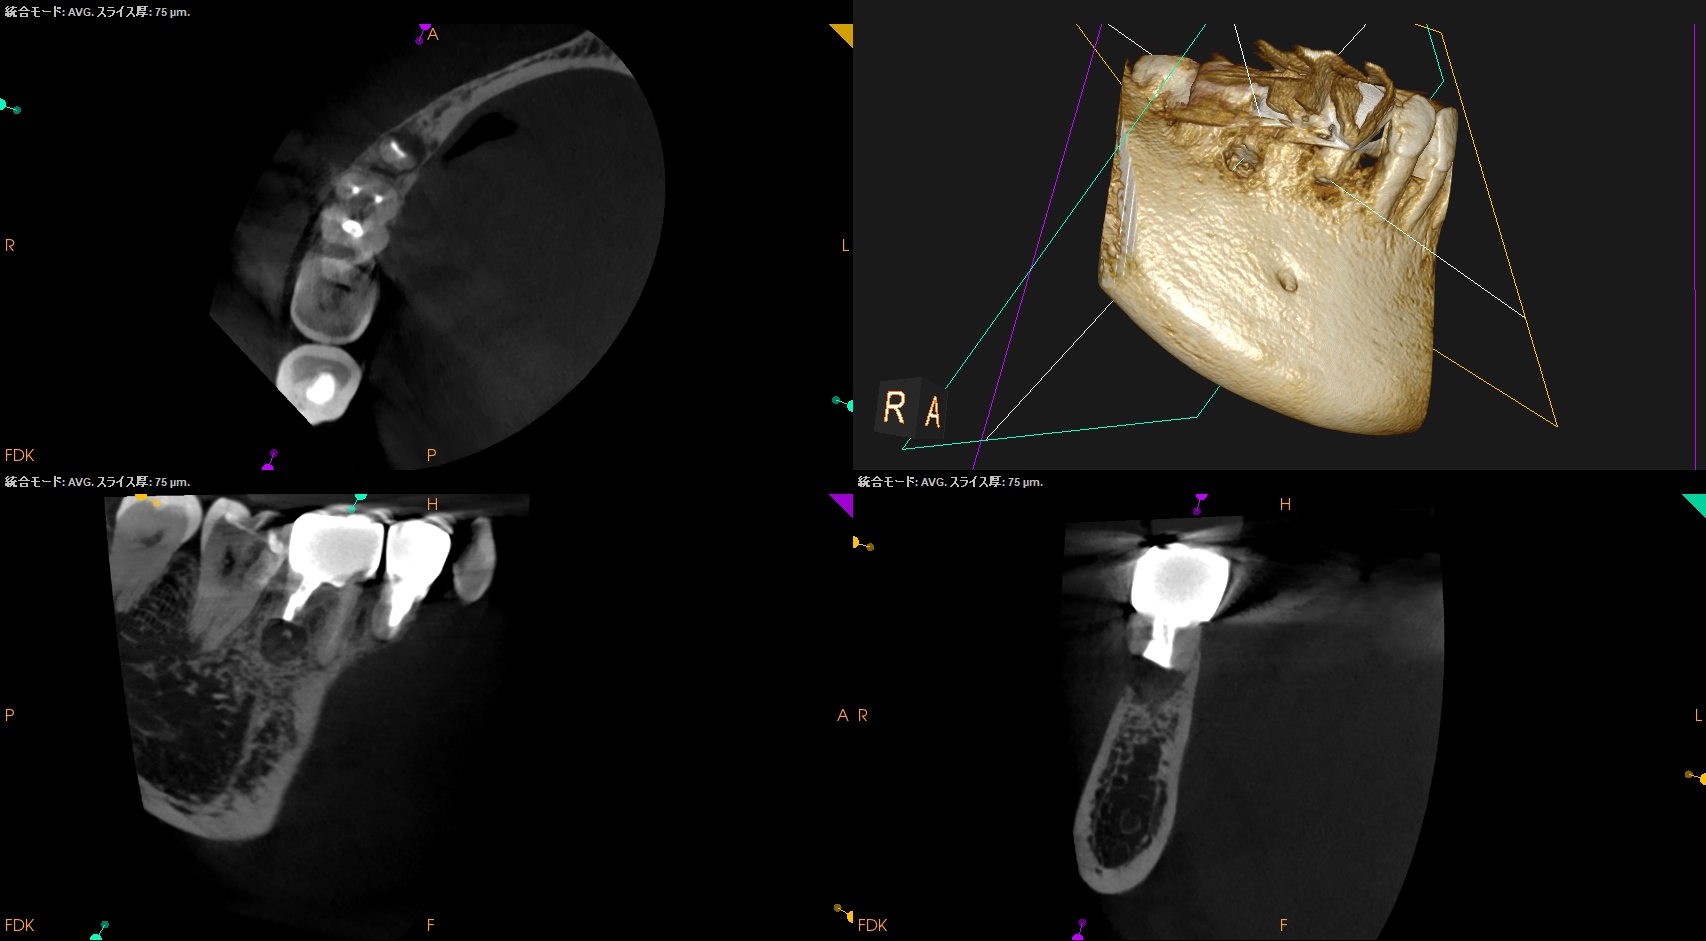

#30 D Apicoectomy 3M recall(2026.1.9)

CBCTも撮影している。

歯槽骨も回復傾向だ。

このまま経過を見ていく。